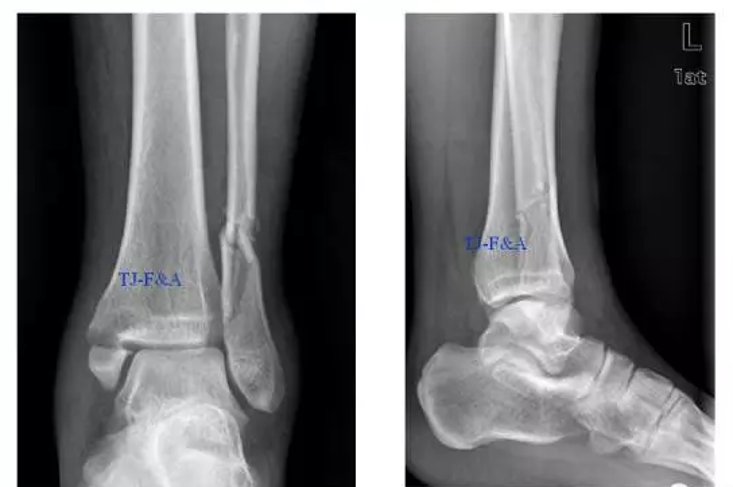

术前DR